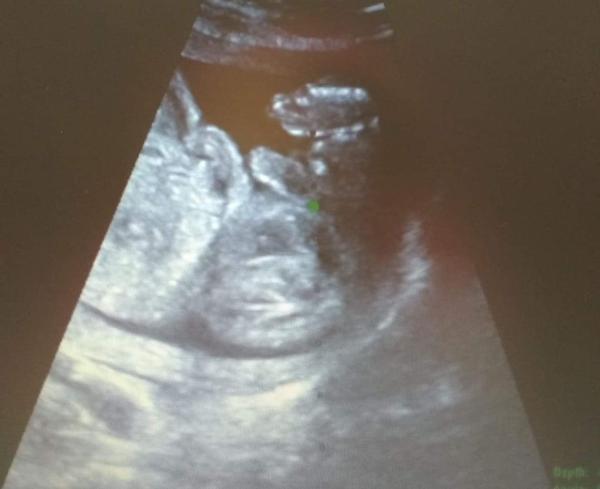

Pohlaví miminka - poznáte ho?

@makronka222 Ruce dokážu lokalizovat, ty mi doktorka na fotce ukázala 🙂. Nohy jsem neviděla, doufám, že je má :D. Já osobně vidím jen rozmazané fleky, ale třeba tu má někdo zkušené oko 🤷♀️.

Z tyhle nekvalitni fotky asi tezko neco vyhledas. Muze tam dole byt ruka, snura, nohy krizem...